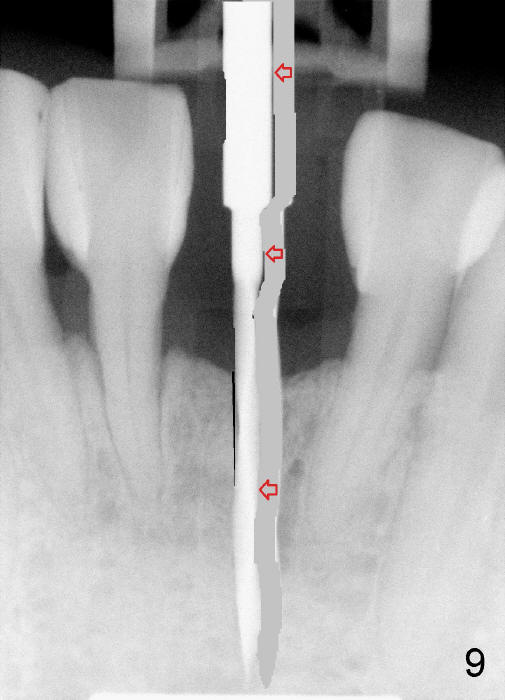

To place the implant correctly, the preop PA should be studied carefully to find the divergence of the roots of the neighboring teeth (Fig.1). The depth of the initial osteotomy should be shorter, for example, 11 mm instead of 14 mm. Once the trajectory is found to be corrected, an incision should be made; the osteotomy is to be overcorrected with Lindermann bur (Fig.8 black); the whole osteotomy is changed with proper angulation (Fig.9 arrows).